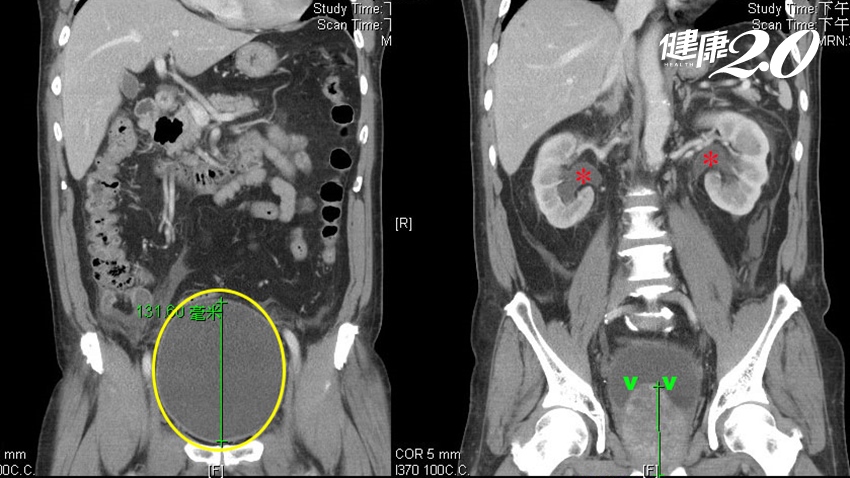

北市聯醫和平婦幼院區泌尿科區許富順提到,一名70歲男性就醫時,攝護腺腫大到正常大小的10倍大,兩周無法順利解尿,在急診插尿管後引流約2,000cc尿液,超音波檢查發現雙腎皆水腫,抽血發現腎衰竭而緊急住院。後續施行第三代綠光雷射氣化切除術、膀胱訓練後才恢復解尿功能,腎臟功能也恢復大半。

▲電腦斷層顯示,患者的攝護腺(綠色箭頭)屬於極重度的肥大,嚴重擠壓到膀胱,導致尿滯留,膀胱脹尿超過2000cc,壓力上傳到腎臟,造成雙側腎臟水腫(紅色星星)。